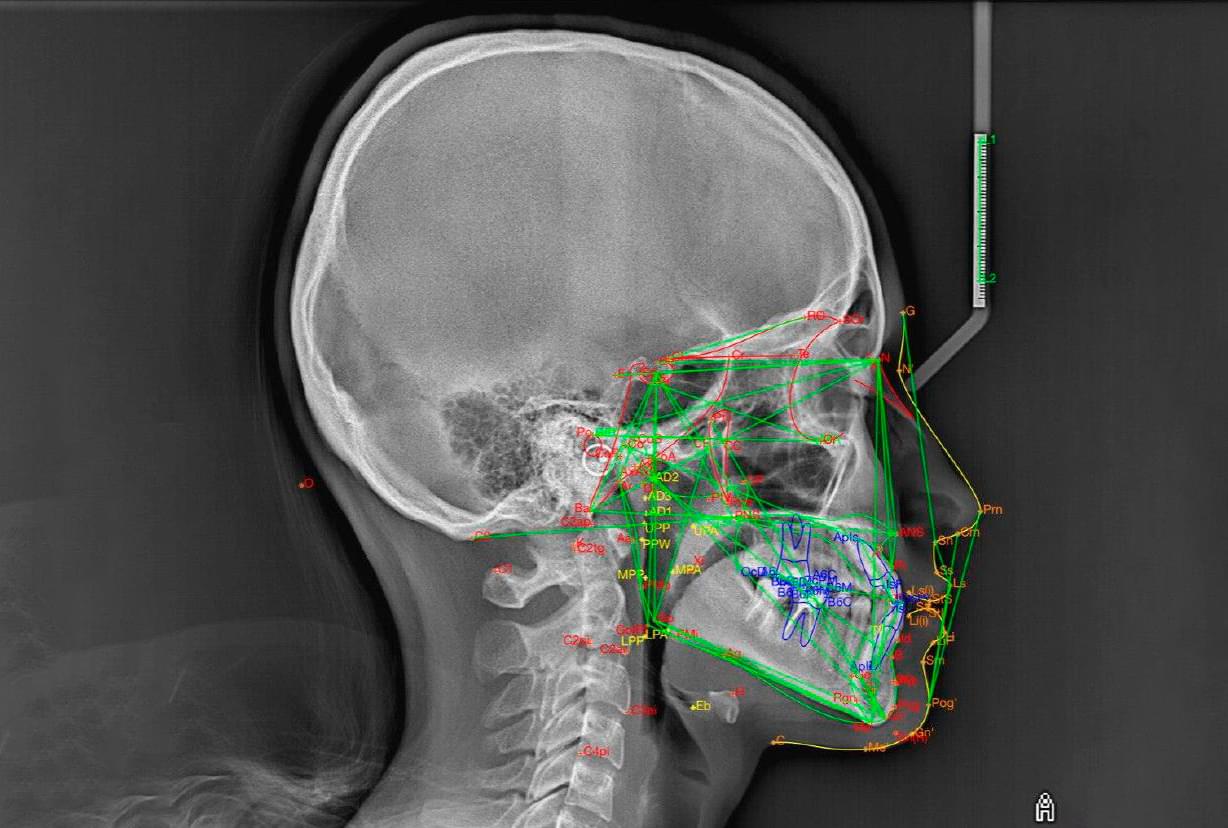

Це окрема діагностична послуга, під час якої лікар-діагност оцифровує знімок, розставляє анатомічні точки та вимірює кути і відстані між кістками черепа та зубами.

✅ Що дає послуга «Розрахунок ТРГ»?

🔹 Індивідуальний план, а не шаблонний. Усі люди різні. Розрахунок показує ваш тип росту

(вертикальний чи горизонтальний), що критично важливо для вибору брекетів або апаратів.

🔹 Прогноз результату. Цифровий аналіз дозволяє змоделювати, як рухатимуться зуби. Це

страхує від помилок і непередбачуваних результатів через рік носіння брекетів.

🔹 Економія часу лікаря - швидший старт для вас. Ортодонт отримує вже готовий звіт з усіма

кутами та параметрами. Йому не потрібно витрачати години на ручне креслення, тому він може

швидше приступити до встановлення системи.